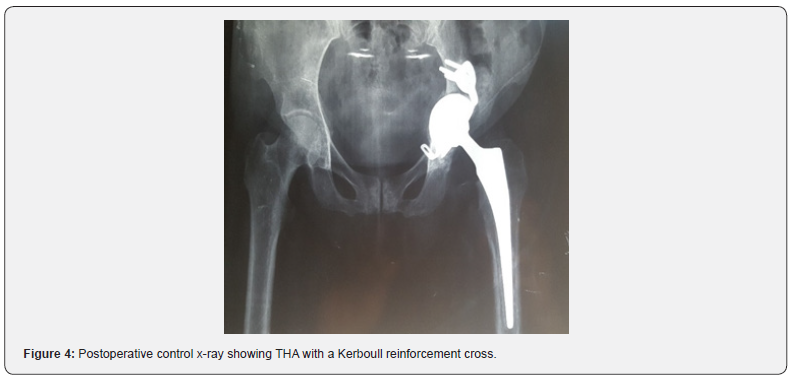

A radiograph of the pelvis showed an acetabular osteolysis with protrusion, destruction of the left femoral head and pathological central dislocation of the hip (Figure 1a). Computed Tomography (CT) revealed irregular Osteolytic process of the acetabulum with an ill-defined border and femoral head destruction, with intra-articular bone fragments (Figure 1b). Magnetic Resonance Imaging (MRI) of the pelvis revealed a remodeling of the left hip in T1 hyposignal and hypersignal in T2 and STIR, moderately enhanced by the contrast product and severe destruction of the femoral head, suggestive of osteonecrosis of the hip (Figure 2). The bone scan revealed increased uptake in the left acetabulum and femoral head, but there were no other suspicious areas of increased uptake to suggest metastases (Figure 3). To eliminate the diagnosis of bone metastasis or Septic arthritis of the hip joint, a CT‑guided biopsy was arranged showing Chronic inflammatory remodeling without evidence of malignancy, with signs related to bone avascular necrosis. Via a standard posterolateral approach, the patient underwent a total hip arthroplasty, by a cemented femoral and acetabular component. In order to fill the bone loss, we used a cemented reconstruction with the addition of a Kerboull reinforcement cross. With use of bone graft from the femoral head (Figure 4). Cultures obtained at the time of surgery were negative. Pathological examination confirmed osteonecrosis. She received twenty days of thrombo-embolic prophylaxis with low molecular weight heparin with Post-operative rehabilitation and fully weight-bearing mobilization immediately after the operation. At 12 months follow-up she had no pain over the left hip and could walk without sticks, the Postel Merle d’Aubigné (PMA) score was 17.